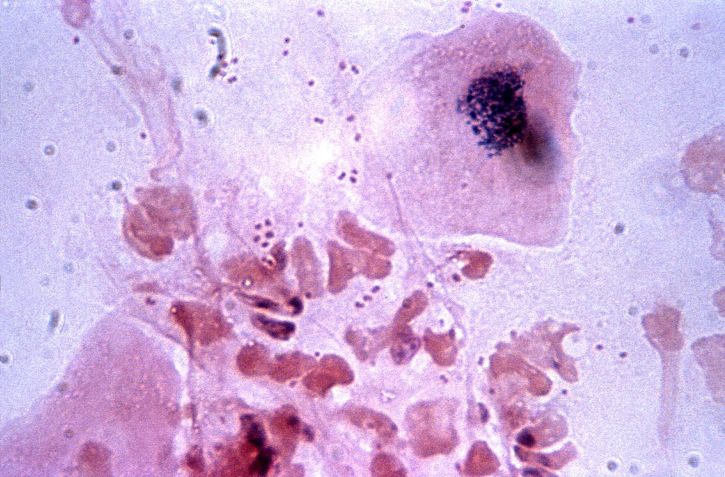

두 번째로 질병에 의한 백혈구 수치 감소가 있습니다. 백혈병과 같은 질병은 백혈구를 생성하는 골수에 영향을 미쳐 백혈구의 생성을 방해합니다. 만약 지속적으로 백혈구 수치가 낮다면, 이러한 질병을 의심해보아야 합니다. 또한 간염과 같은 간 질환도 백혈구 수치에 큰 영향을 미칠 수 있습니다. 간은 백혈구 생성을 위한 중요한 역할을 하는 기관이므로, 간에 문제가 발생하면 자연스럽게 백혈구 수치도 감소하게 됩니다.